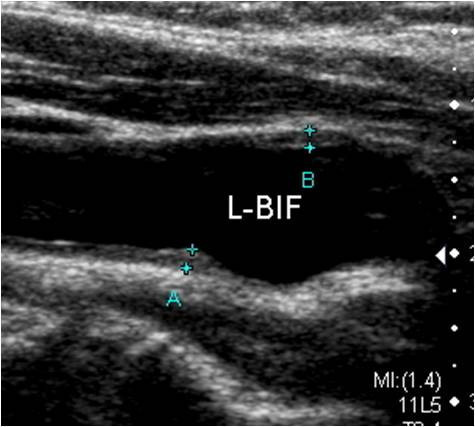

경동맥 초음파(Carotid Ultrasound)는 목 양쪽에 위치한 경동맥(carotid artery)의 혈류 상태를 확인하는 비침습적 영상 진단법입니다. 경동맥은 뇌로 혈액을 공급하는 주요 동맥으로, 이 부위에 죽상경화(동맥경화)가 발생하면 뇌졸중(중풍)이나 일과성 허혈 발작(TIA) 등 치명적인 뇌혈관 질환으로 이어질 수 있습니다.

이 검사는 초음파를 통해 경동맥 내벽의 두께, 혈류 속도, 혈전이나 협착(좁아진 부분) 여부 등을 정밀하게 경동맥 초음파 검사로 알 수 있는 병들을 관찰하여, 뇌졸중 위험성을 사전에 파악할 수 있는 중요한 예방 의료 행위입니다.

5. 혈관 노화 지표

- 내중막 두께(IMT) 측정으로 혈관 노화 정도를 정량화할 수 있습니다.

- 판독 및 상담

- 의사가 협착 정도 및 IMT 수치, 혈류 이상 등을 설명